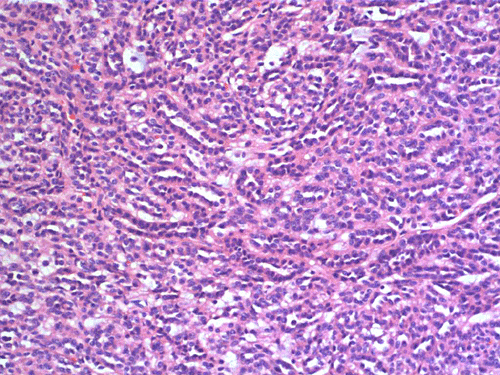

Two major patterns are revealed. In the first pattern, the tumor cells grow in a densely packed tubular pattern with mucinous content (Panel A and B). In some other areas, the tubular pattern is replaced by interlacing fascicles of spindle cells separated by mucinous pools (Panel C and D). In some areas, the spindle cells are solidly packed (Panel E). In both areas, the nuclear are bland in appearance and without significant mitotic acivity. The tumor cells, both in the spindle cell area and tubular areas are strongly positive for cytokerain AE1/AE3, cytokeratin 7, Cam5.2, and epithelial membrane antigen (EMA) respectively (Panel F, G, H and I). The tumor cells are also negative for synaptophysin (Panel J and K) and CD10 (Panel L and M). The positive cells in Panel M are residual non-neoplastic renal tubules. The Ki67 labeling (Panel N) is low (about 1-2%).

These tumors have very characteristic histologic patterns comprised of cuboidal and spindle cells. The cuboidal cells tend to form tubular growth patterns, although trabercular and solid patterns can be identified. Sheets of spindle cells often intersperse between interconnecting tubules, leading to a biphasic appearance. The cells are characterized by eosinophilic cytoplasm, small to medium sized nuclei with little to no atypia, and occasional prominent nucleoli. The surrounding stroma is predominantly myxomatous with a bubbly quality and stains consistently with alcian blue. Studies have shown that a wide majority of MTSCC tumors are positive for epithelial membrane antigen (EMA), AE1/AE3, and cytokeratin 7. In contrast to the classic type of renal cell carcinoma, only about 15% of these tumors are positive for CD10 5. Expression of neuroendocrine markers has also been demonstrated in some tumors 6, 7. Other immunohistochemical markers may be variably positive, including E-cadherin, vimentin, and Ulex Europeus agglutinin-1 (UEA-1). These tumors have a low MIB-1 labeling index. In general, there is not a single marker that could confidently separate this tumor from other renal tumor. The final diagnosis must rest on considerations of morphological and immunohistochemical evidence.